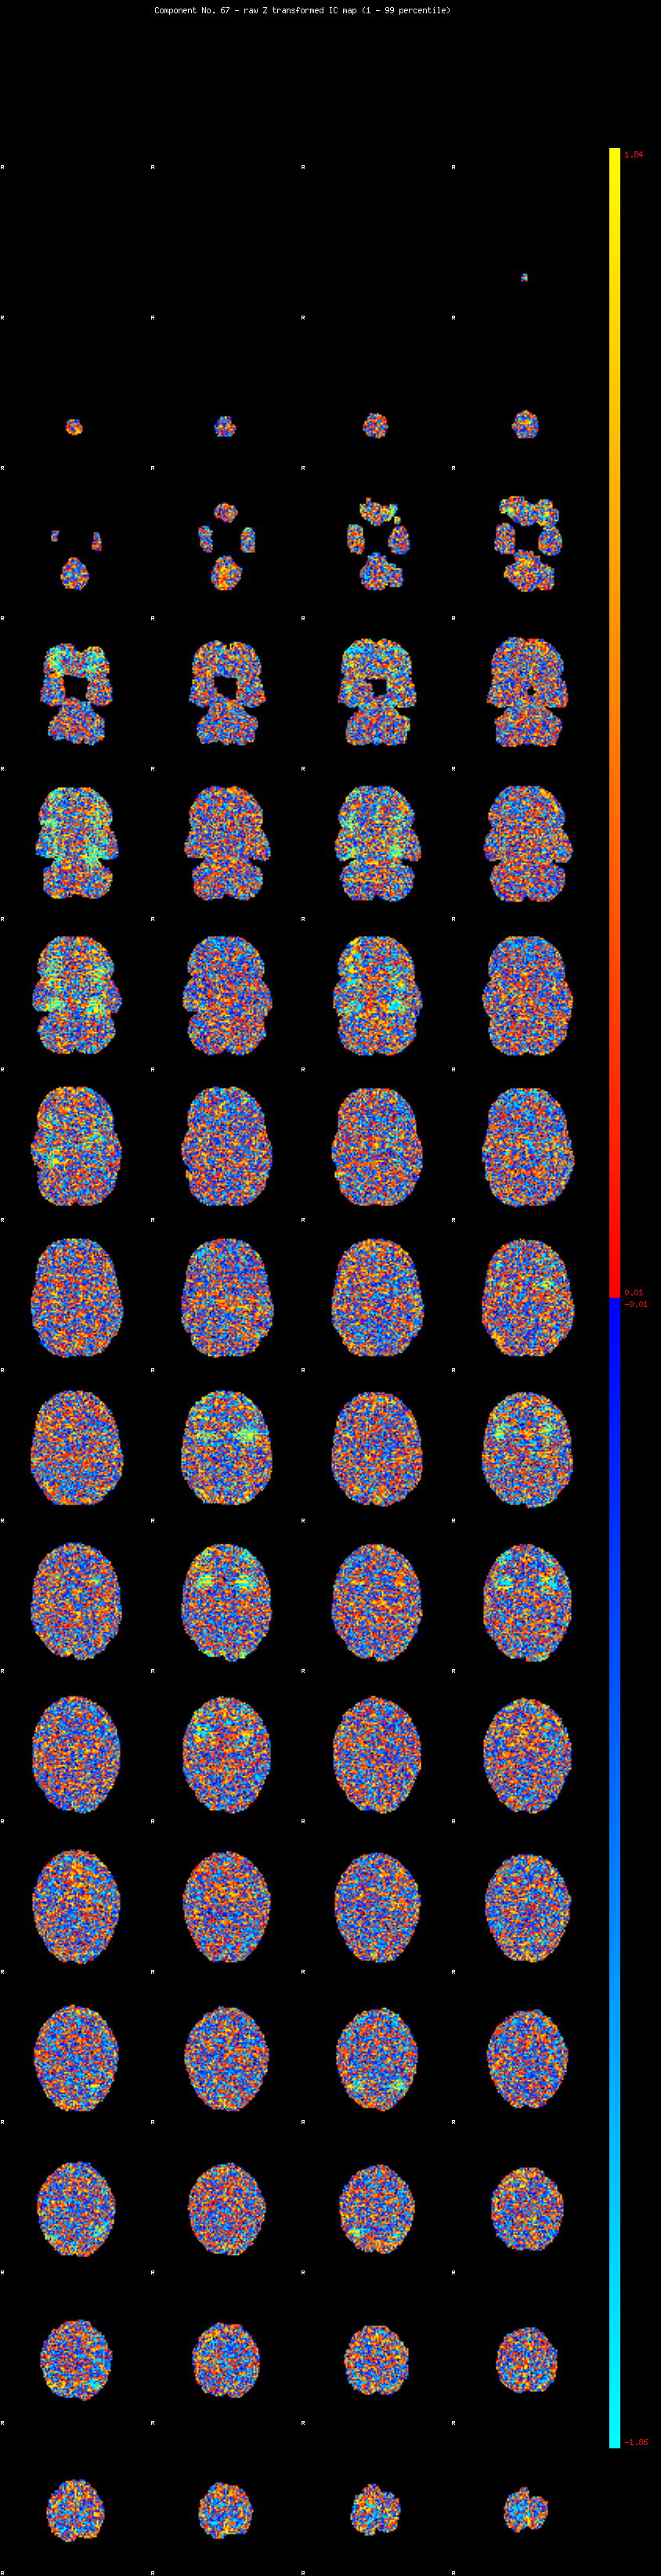

IC_67 Mixture Model fit

Means : 0.000000 2.467823 -2.721875

Vars : 1.000000 2.066205 2.965601

Prop. : 0.969186 0.015557 0.015258